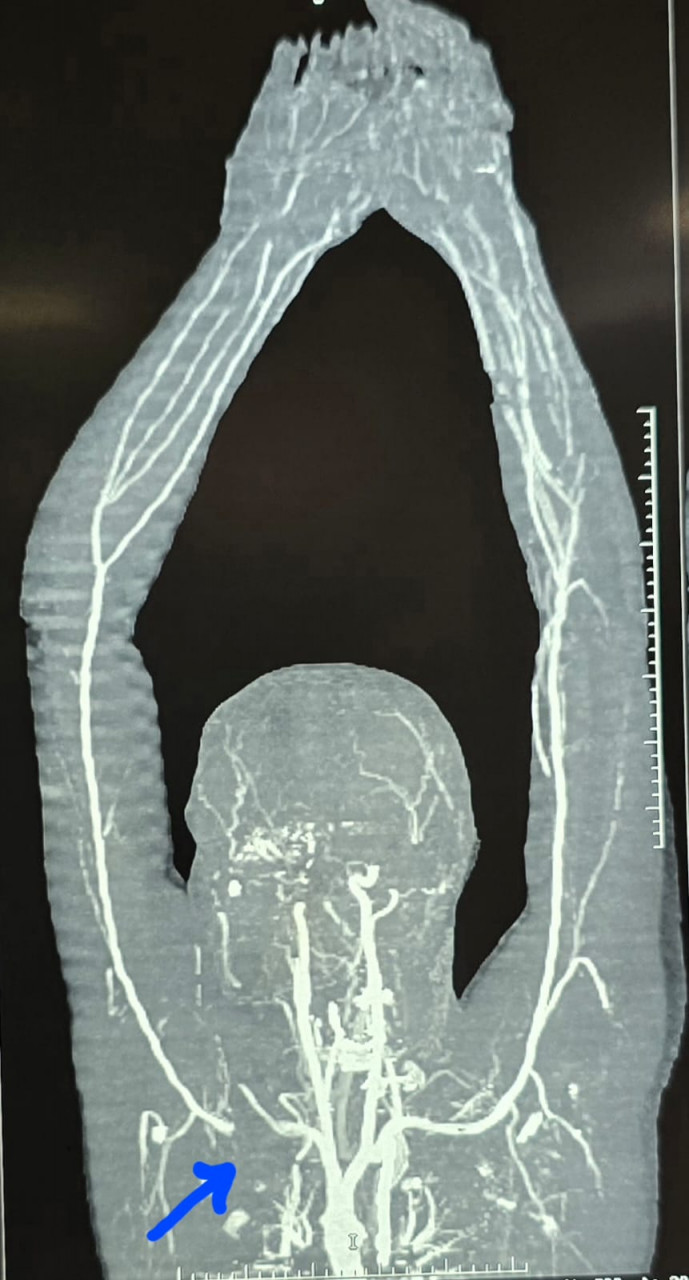

डॉ. कृष्णकांत साहू के नेतृत्व में सर्जरी टीम ने सबक्लेवियन आर्टरी की गंभीर क्षति को जोड़ते हुए कॉलर बोन को काटकर धमनी तक पहुंच बनाई। ऑपरेशन के दौरान लगभग 5 यूनिट रक्त चढ़ाया गया और 4 घंटे की मेहनत के बाद हाथ में रक्त प्रवाह बहाल किया गया। कॉलर बोन को प्लेट के माध्यम से पुनः जोड़ा गया, और तंत्रिका तंत्र सुरक्षित रखा गया।

डॉ. साहू ने बताया कि यदि समय पर उपचार नहीं हुआ होता, तो मरीज का हाथ कटने की संभावना थी। इस सर्जरी में ऑर्थोपेडिक सर्जन, एनेस्थेटिस्ट, जूनियर डॉक्टर और नर्सिंग स्टाफ की समन्वित टीम ने अहम भूमिका निभाई।